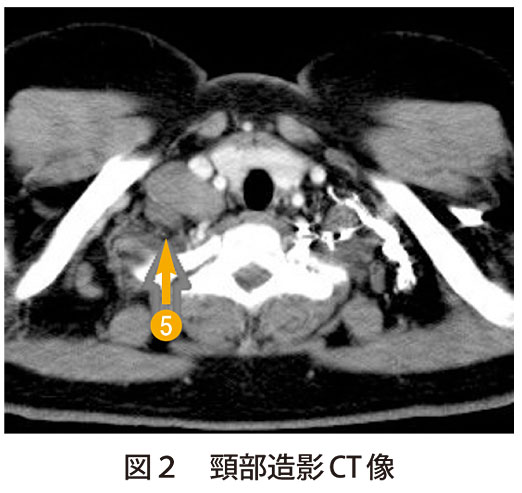

解答 解説 発熱 咳嗽を主訴に受診した70歳代男性 実践 画像診断q A 羊土社 レジデントノート 羊土社